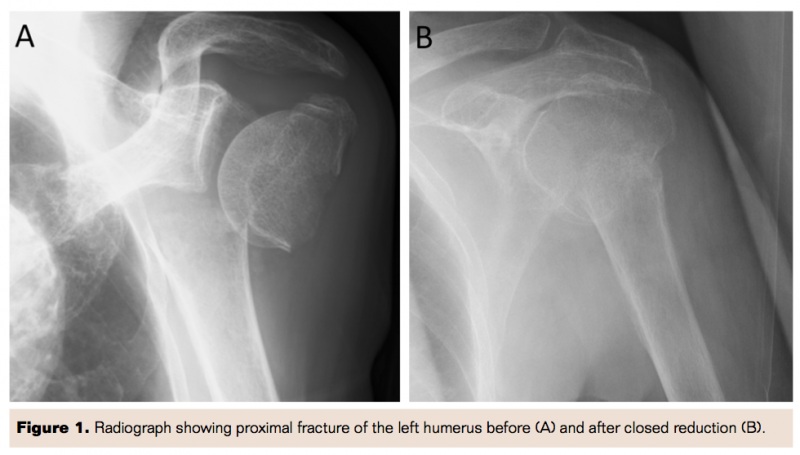

An 82-year-old Japanese male presented with severe pain in the left shoulder and arm, with discoloration of hand and fingers, 2 hours after falling at home. His medical history included osteoporosis and prostate cancer that were well controlled with medical treatment. On admission, his vital signs were stable. On physical examination performed approximately 2 hours after the fall there were no brachial, radial, or ulnar pulses in the left arm. There were no open wounds. The hand and forearm were pale and cool, but the skin of the fingers was dark, indicating critical ischemia. In spite of mild hypoesthesia, there was no weakness in his hand and fingers. His hemoglobin was 9.6 g/dL and the estimated glomerular filtration rate was 71.9 mL/min/1.73 m2. The serum creatine kinase level was 123 IU/L. An initial radiography of the left shoulder revealed a three-part fracture of the left proximal humerus with severe medial displacement, according to Neer classification. To restore blood flow, he underwent immediate closed reduction under interscalene brachial plexus block (Figure 1). However, the distal pulses were still not palpable and the fingers remained dusky. An early phase contrasted computed tomography (CT) scan showed an abrupt obstruction of the left axillary artery adjacent to the fracture site, without evidence of contrast extravasation. This finding suggested occlusion associated with an intimal tear caused by the displaced shaft of the humerus rather than arterial transection. Late-phase contrasted CT images revealed a faint visualization of the brachial artery distal to the occluded axillary artery (Figures 2 and 3). His upper limb was thought to be salvageable because of the lack of weakness in his left hand and fingers.